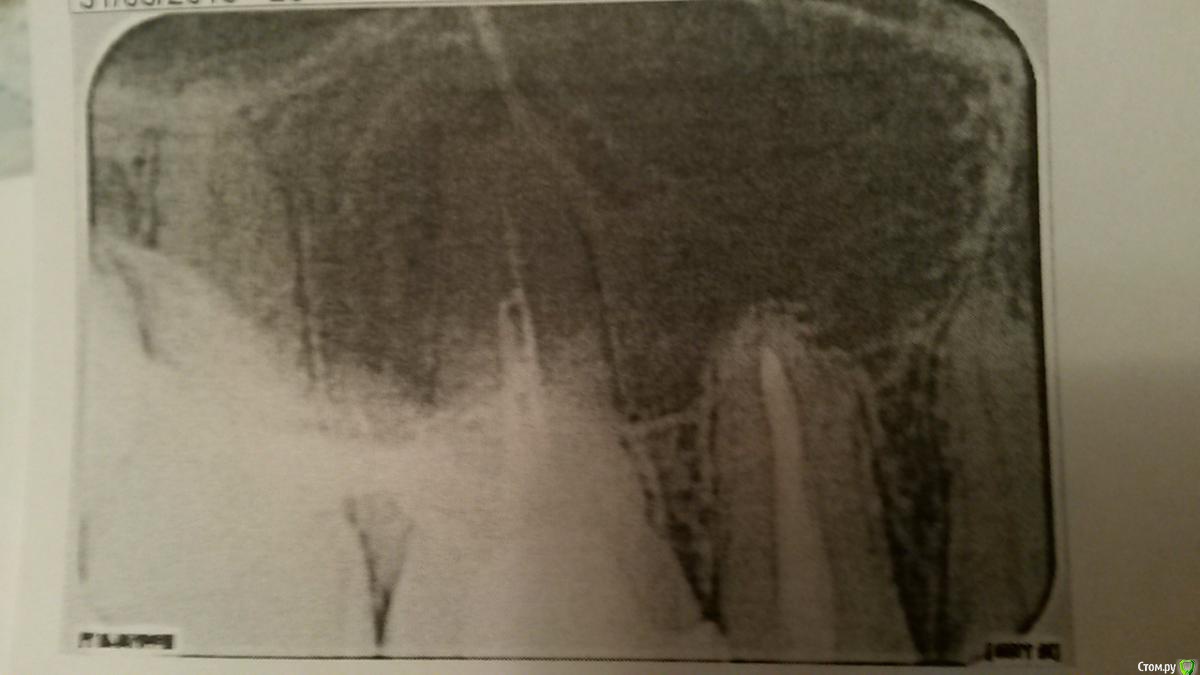

alexandrovna Опубликовано 31 марта, 2015 Автор Поделиться Опубликовано 31 марта, 2015 (изменено) Сделала снимок. Правда дали распечатку не очень хорошего качества и возможности отсканировать пока нет. Доктор сказал над 26 зубом очаг инфекции, пропить нимесил, перелечить зуб. Еще показалось ему (доктору), что в одном канале (по середине который) обломок инструмента и вообще, он полупустой. Не поможет-вырывать. Изменено 31 марта, 2015 пользователем alexandrovna Ссылка на комментарий

Гарриевич Опубликовано 31 марта, 2015 Поделиться Опубликовано 31 марта, 2015 однозначно перелечивать Ссылка на комментарий

alexandrovna Опубликовано 1 апреля, 2015 Автор Поделиться Опубликовано 1 апреля, 2015 однозначно перелечивать А нимесил пить? Просто мы прочитали инструкцию - там про инфекцию не слова, только про снятие болевого синдрома. И действительно может так быть, что лечение не поможет и придётся удалять зуб? И еще такой вопрос-можно как-то отметить проблемные зоны на снимке, чтоб я могла показать их врачу, а не стояла и не слушала, что "всё в порядке, так и должно быть". Спасибо большое. Ссылка на комментарий